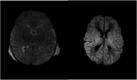

Case Report: Disseminated herpes simplex virus complicated by hemophagocytic lymphohistiocytosis in a neonate

Neonatal herpes simplex virus (HSV) infection carries a high mortality rate due to its potential to cause disseminated disease involving multiple organ systems, which can rapidly progress to shock and death if not promptly treated. In rare cases, neonates may mount an uncontrolled inflammatory response leading to hemophagocytic lymphohistiocytosis (HLH), a severe hyperinflammatory syndrome. We present a case of neonatal HSV infection complicated by HLH, highlighting the challenges of managing both conditions concurrently. Our therapeutic approach demonstrated a reduction in systemic inflammation and viral load; however, despite these efforts, the patient developed multiorgan failure and ultimately died from the initial disease process. This case underscores the severity of neonatal HSV infection and emphasizes the critical role pediatricians play in early identification of transmission risk factors and prevention strategies.